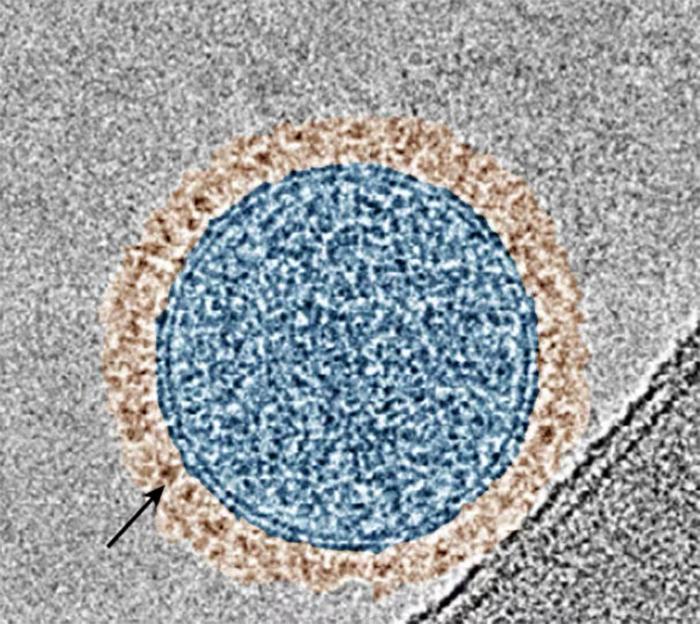

A color-enhanced microscope image showing an exosome (in blue) with PD-1 proteins on its surface (in brown). The black arrow points to the ring of PD-1.

Credit: Cheng Lab/Columbia Engineering

In the current study, published today in the journal Nature Biotechnology, Cheng and his colleagues created an exosome system that co-displays two therapeutic proteins to treat lung metastases. One protein blocks the PD-1/PD-L1 immune checkpoint pathway, a process that has been shown to boost the immune response against melanoma cells and shrink tumors. The other protein blocks the Wnt/β-catenin signaling pathway that drives immune exclusion in tumors, a phenomenon where immune cells are unable to infiltrate tumor tissues.